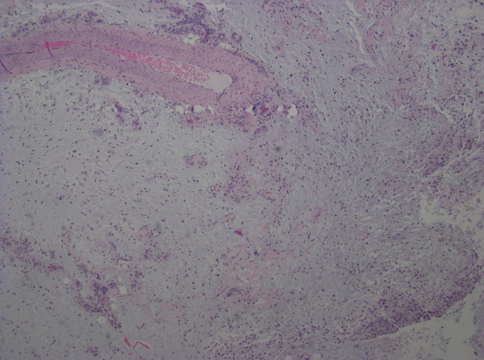

Surgery included dissection of the subdermal layer, which revealed dark, yellowish, lipomatous and gel-like viscous tissue. The mass lacked a discernible capsule and appeared amorphous in nature. The preliminary report from the pathologist characterized the mass as having a myxoid tissue consistency of uncertain origin (Figure 2). However, there was a high suspicion for myxoinflammatory fibroblastic sarcoma. The specimen was subsequently submitted to the pathology department at Johns Hopkins University Hospital for definitive diagnosis, which indeed confirmed the presence of a myxoinflammatory fibroblastic sarcoma (Figures 3, 4, 5). A follow-up MRI after the surgery, ordered by the consulting orthopedic oncologist, revealed postsurgical changes related to the recent tumor resection along the dorsal aspect of the ankle joint. The MRI also indicated postoperative edema without the identification of any discrete drainable fluid collection.